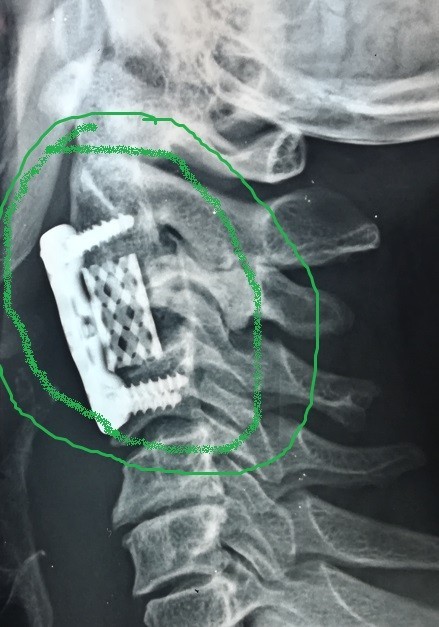

تثبيت امامي لكسر وتاكل بجسم الفقرة الثالثة العنقية

anterior fixation of a fracture and wear of the body of the third cervical vertebra

A successful anterior fixation surgery was performed to treat fracture and erosion in the vertebral body of cervical vertebrae. This specialized procedure aims to restore cervical spine stability and address vertebral damage resulting from injury or inflammation.

• Advanced internal fixation using plates and screws

• Replacement of damaged vertebral body with bone graft or implant